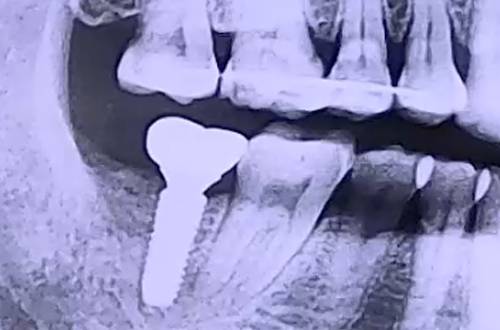

BEFORE

6개월 정도 전에 발치한 오른쪽 아래 어금니에 임플란트를 하기 위해

저희 병원에 내원해 주셨던 환자분이십니다.

발치하신 자리의 잇몸뼈 상태는 아주 좋았기 때문에

임플란트 식립에도 문제가 없는 심플한 케이스였는데요.

발치했던 어금니와 맞닿는 위 어금니가 흔들거리고 있었습니다.

비어 있는 공간 탓에 중력의 힘을 받으며 이가 약해지고

아래로 점점 내려오고 있었기 때문인데요.

임플란트가 굳기를 기다리는 동안 윗니가 내려오게 될 가능성을 고려하여

윗니를 잡아 줄 와이어를 앞쪽 치아와 이어 붙여드렸습니다.